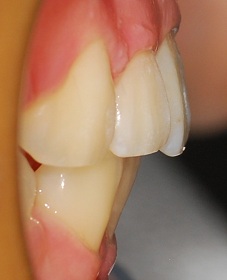

완성된 치아사진 보실게요ㅎㅎㅎ

측면사진